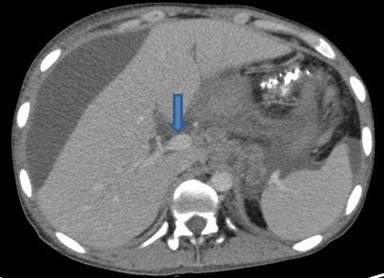

A 30-year-old man presented to our outpatient clinic with history of abdominal distention without pedal edema for the past 3 months. He also had deep boring epigastric pain and vomiting for 2 months. He had noticed low grade fever and anorexia for last 15 days. He had been consuming alcohol (100 g/day) for last 5 years (last drink 3 months back). Examination revealed pallor, facial puffiness, tachycardia, ascites and bilateral pleural effusion. His neck veins were engorged and hepatojugular reflex was absent. On investigation ascitic fluid was hemorrhagic with proteins 5.5 g/dL (reference range: 0-0.5 g/dL); white blood cells were 215 mm-3 (reference range: 0-5 mm-3; polymorphs 35% and lymphocytes 65% in a background of red blood cells). Ascitic fluid adenosine deaminase was 20 IU/mL (reference range: 0-35 IU/mL) and ascetic fluid amylase 58,840 IU/L (reference range: 0-100 IU/L). Pleural fluid was also hemorrhagic with protein 5.5 g/dL (reference range: 0-0.5 g/dL), white blood cells 80 mm-3 (polymorphs 50%, lymphocytes 50%) and adenosine deaminase was 35 IU /mL. 2D echo was normal. Serum amylase was 700 IU/L (reference range: 0-150 IU/L), serum lipase was 3,526 IU/L (reference range: 0-150 IU/L), and pleural fluid amylase was 5,748 IU/L (reference range: 0-50 IU/L). CT scan showed thromboses of bilateral subclavian and internal jugular vein, superior vena cava, infra renal inferior vena cava, a segment of suprarenal and infrahepatic inferior vena cava and right common iliac vein and patent splanchnic veins (Figures 1-5). Color Doppler abdomen showed normal portal vein of 10 mm diameter with hepatopetal flow, normal retrohepatic inferior vena cava with hepatopetal flow, while rest of inferior vena cava was thrombosed; all three hepatic veins well visualized with normal flow (Figure 6). MRCP revealed acute inflammation with underlying chronic pancreatitis with stricture at junction of head and body with intraductal calculi with leak at head and body junction and multiple loculated intra abdominal collections. The prothrombotic work up, including factor V Leiden, JAK 2 mutation, homocysteine, antiphospholipid antibody, protein C and S, and antithrombin III, was negative. Thus, a diagnosis of chronic pancreatitis with pancreatic ascites and pleural effusion with multiple extrasplanchnic thromboses due to pancreatitis was made. Patient was managed conservatively with intravenous heparin, initially continuous infusion of 1,000 units/hour and later on oral anticoagulants. ERCP with pancreatic sphincterotomy was done and a 5Fr x 10 cm stent was placed. Patient symptomatically improved with complete disappearance of ascites. His repeat color Doppler showed partial recanalization of superior vena cava, internal jugular vein and subclavian veins (Figure 7).

Figure 2. CECT axial view depicts patent splenic vein (arrow), the pancreas is ill defined with surrounding ascites. |